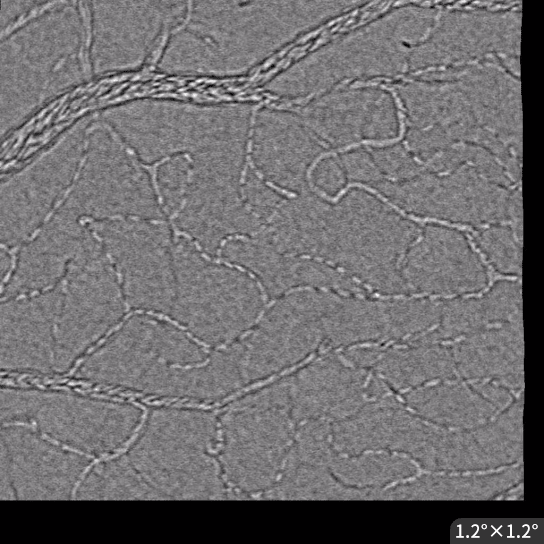

Reflectance